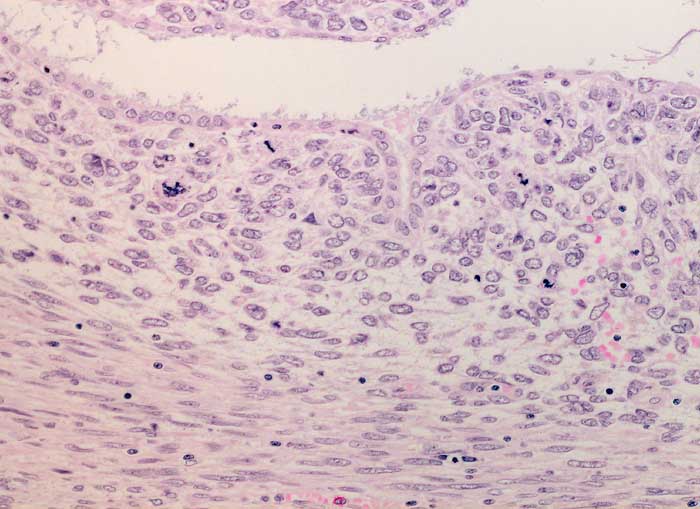

Adenosarkom

maligner Tumor

Uterus

In diesem Bildausschnitt ist eine von gutartigem Epithel ausgekleidete Zyste erkennbar. Das angrenzende Stroma ist verdichtet (Kambiumschicht), weist ausgeprägte Atypien und mehrere, teils atypische Mitosen auf.

Postmenopausale Blutungsstörung, sonographisch suspekter Endometriumbefund, klinisch V.a. Endometriumkarzinom.

Histologie

200